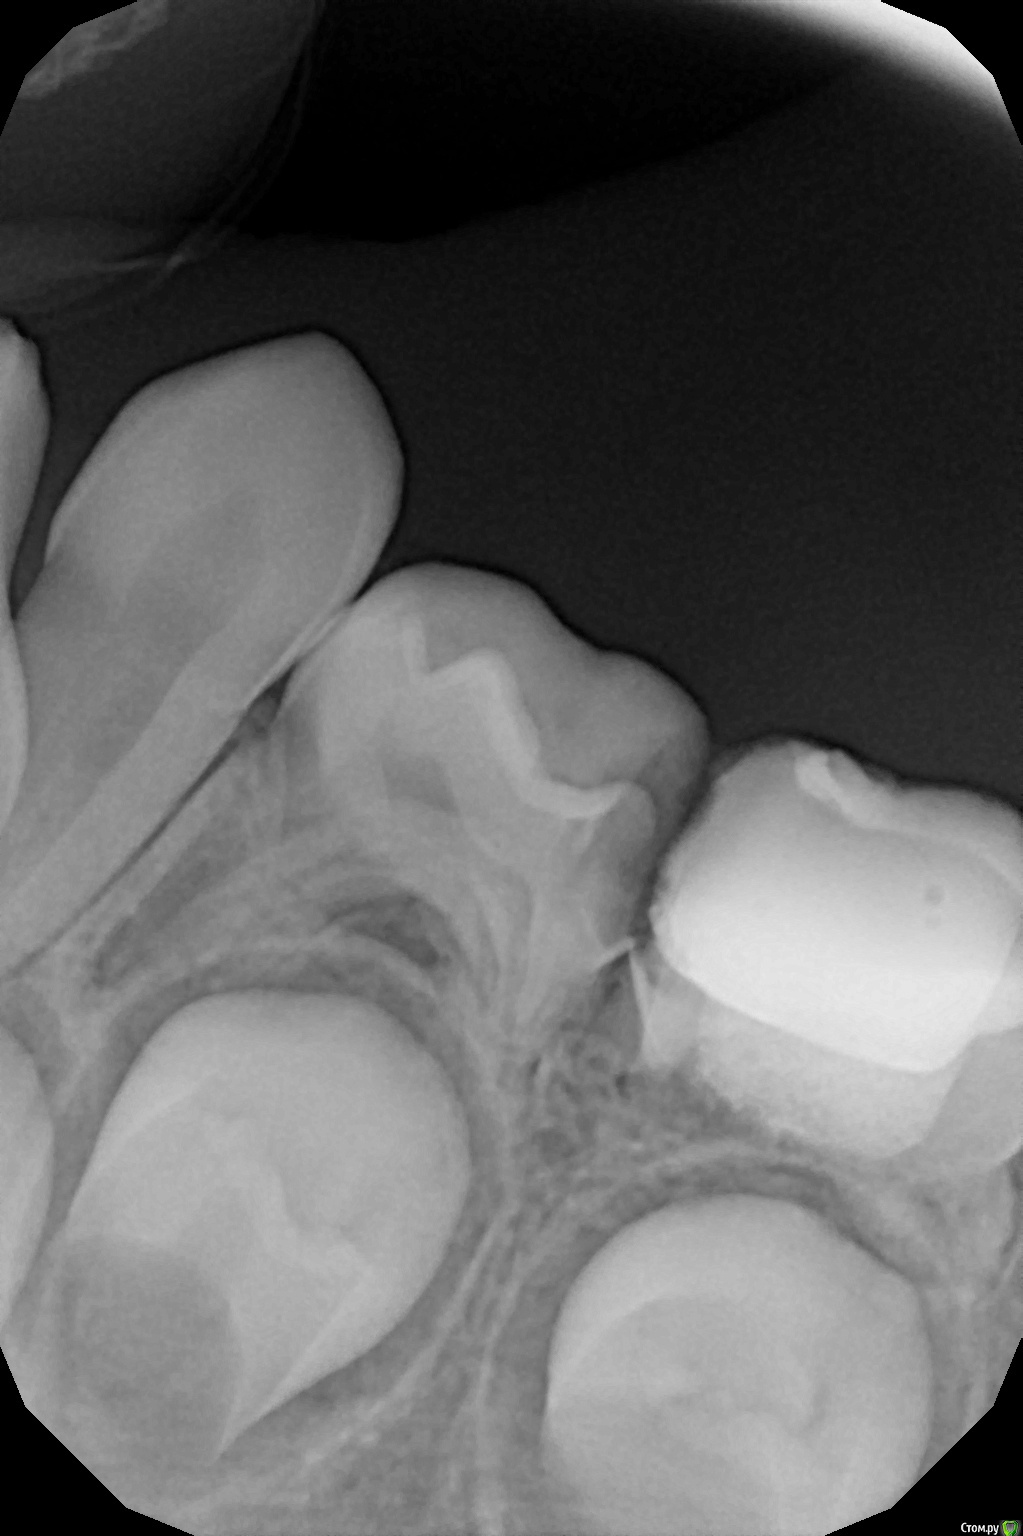

crown Опубликовано 15 июля, 2016 Поделиться Опубликовано 15 июля, 2016 Год назад пришли с периодонтитом 75, зуб был вскрыт в одной точке, до этого ходили полоскали, на рентгене почти полная резорбция, в бифуркации разрежение. Я не знаю зачем начал лечить его, вдобавок ко всему еще перфонул бором прям по середине (рукожоп). Вообщем "зарезорцинил" его, перфорацию и устья промыл гипохлоритом и закрыл триоксидентом. Вот пришли через год лечить соседний 74, а это стоит и не беспокоит, вот такой вот огрызок. Планируется на нижнюю челюсть заместительная пластинка, т.к. нет зубов на другой стороне, вот теперь не знаю удалять его или доживет? 3 Ссылка на комментарий

CRAZYDUCK Опубликовано 16 июля, 2016 Поделиться Опубликовано 16 июля, 2016 Не надо удалять ,на снимке все спокойно .в крайнем случае всегда можно к пластинке еще один зуб добавить.я уверена ,что с зубом все хорошо будет Ссылка на комментарий

Джима Опубликовано 17 июля, 2016 Поделиться Опубликовано 17 июля, 2016 crown, просто класс! чёт в голову не приходило, что ведь и так тоже можно делать. Супер!взрослым терапевтам не понять. год - это тоже срок, это ж год жизни ребёнка - для них огромный срок. Ссылка на комментарий